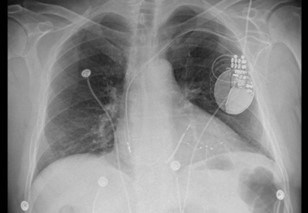

Röntgen-Aufnahme des CRT-Gerätes